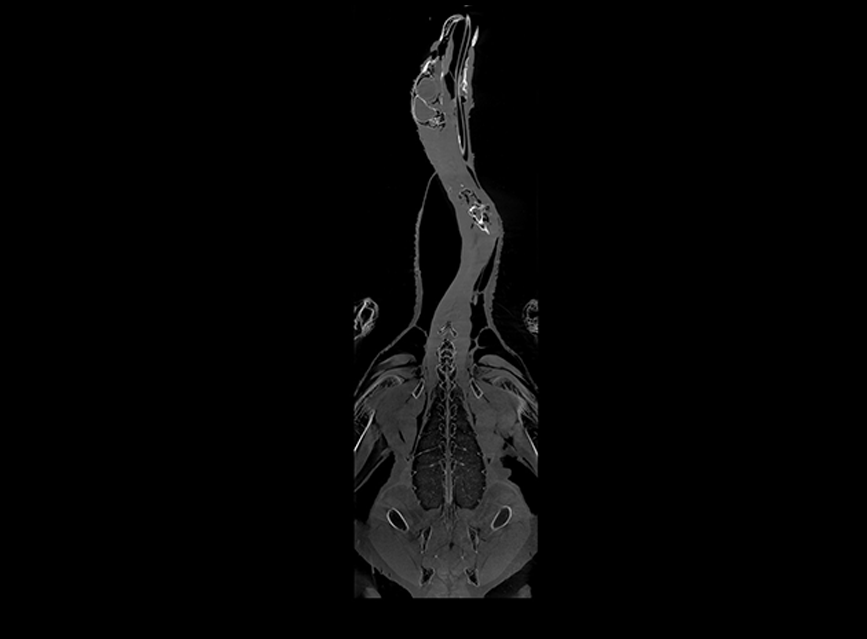

Our High Definition Volumetric Imaging (HDVI) technology is the most advanced form of Flat Panel CT technology. It delivers high-quality diagnostic imaging for both hard and soft tissues. This technology includes specific presets and customizable accessories designed for zoo animals.

High Definition Volumetric Imaging (HDVI) Computed Tomography and Fluoroscopy in one device.

Outstanding image quality in hard and soft tissues with a spatial resolution up to 100 μ.